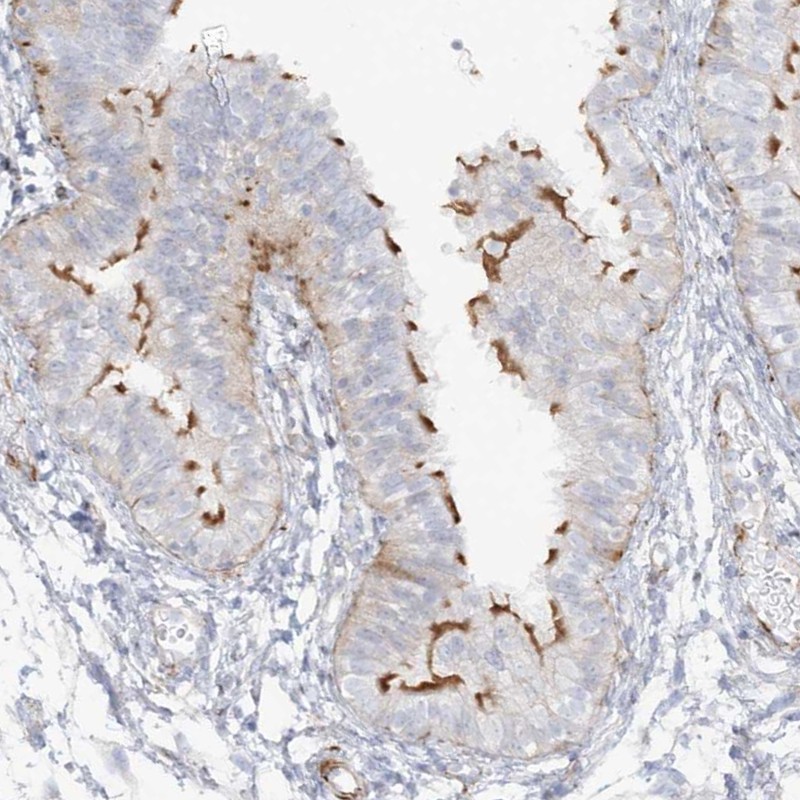

Immunohistochemical staining of human fallopian tube shows distinct positivity in ciliated cells.